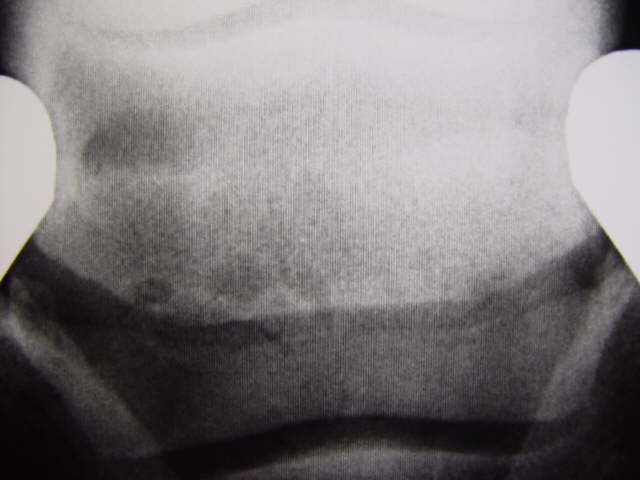

Oseolytische Defekte

Osteolytische Prozesse am unteren Strahlbeinrand und randständiger erweiterter Gefäßkanal. Röntgenklasse IV